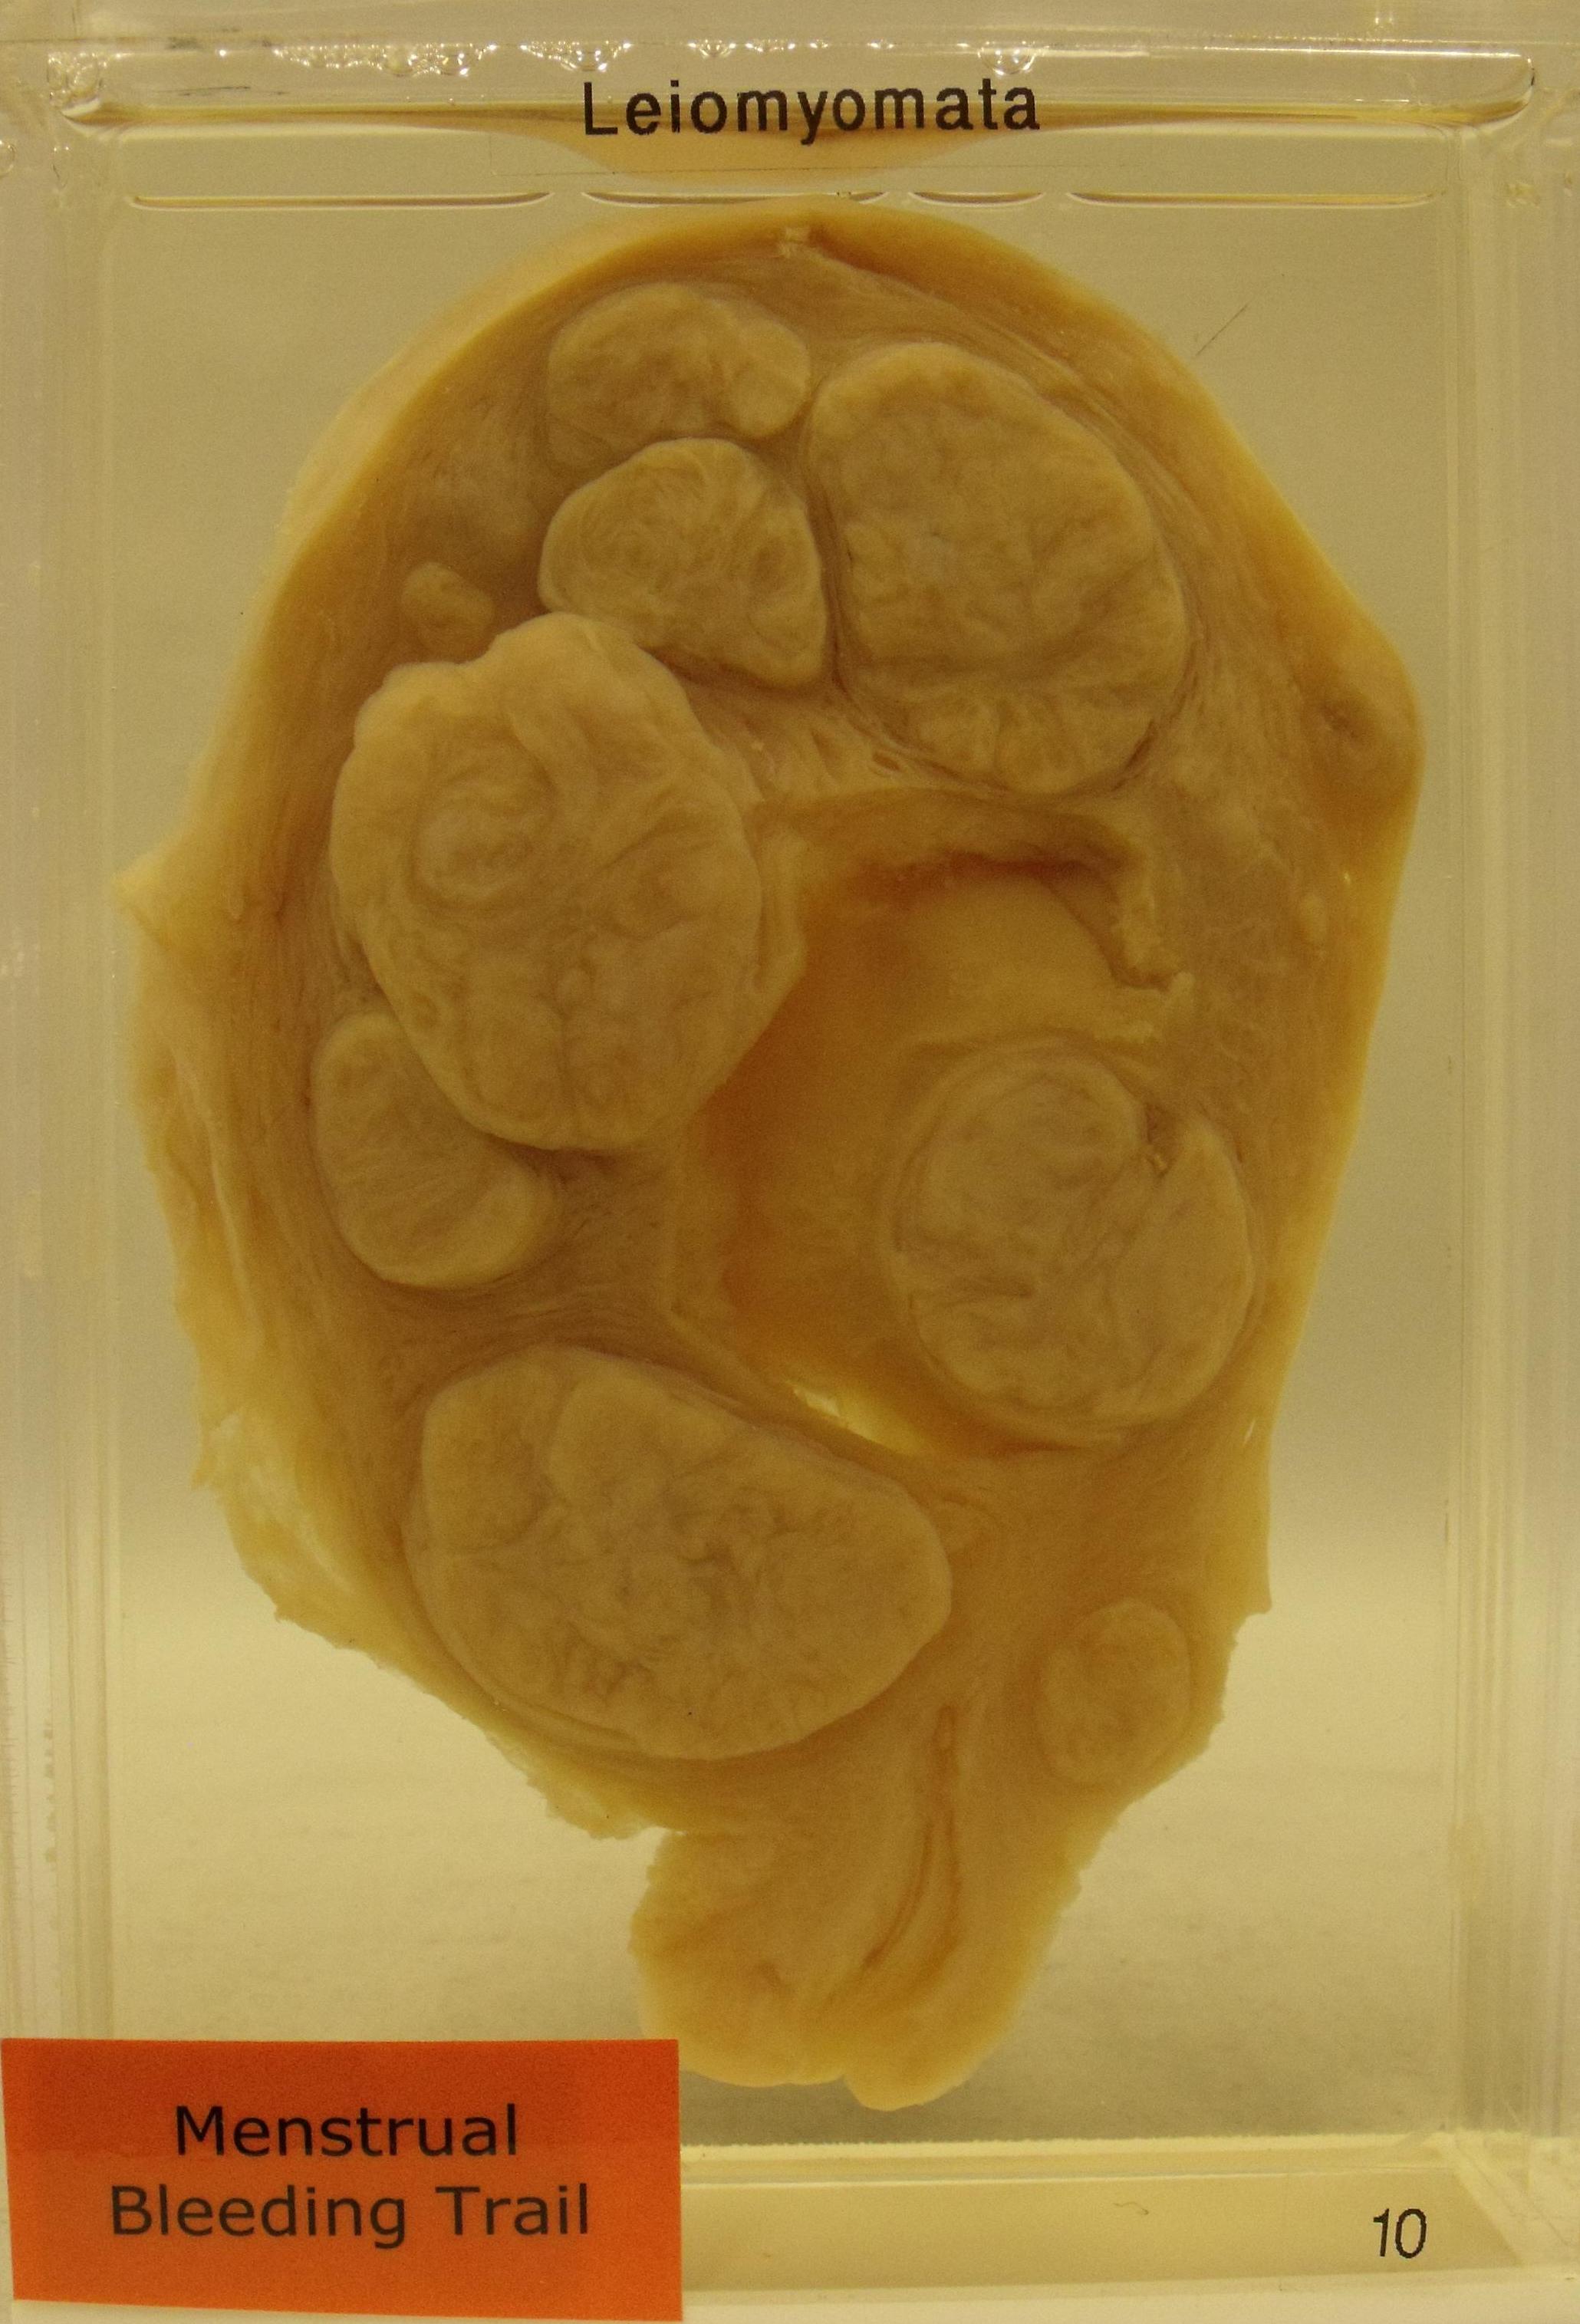

Uterine Leiomyomas

histocutup.co.uk

histocutup.co.uk

fibroids uterus fibroid cut surface leiomyoma uterine leiomyomas specimen protrusion contains myometrium characteristic nine above